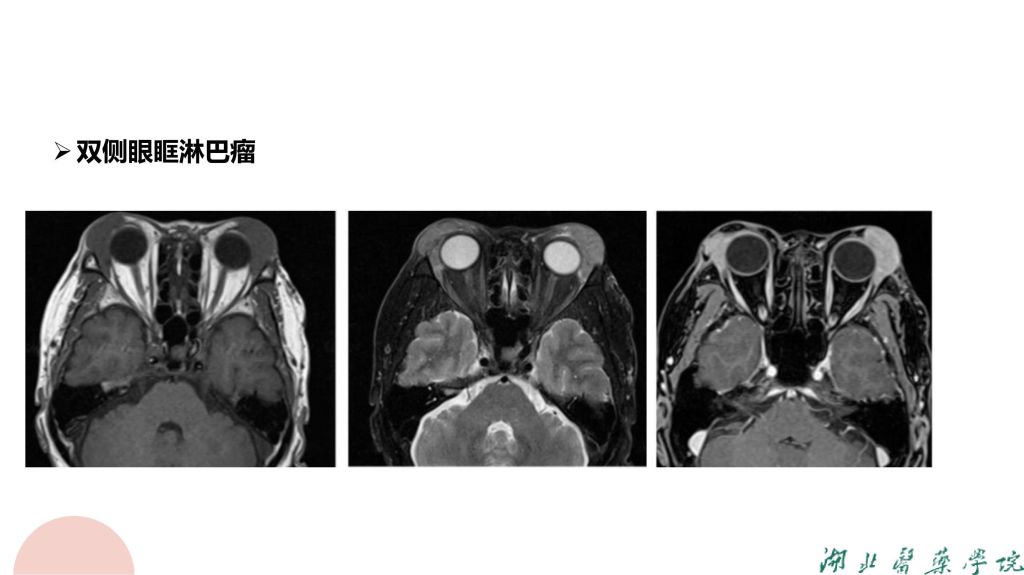

病例分析-眼眶淋巴瘤